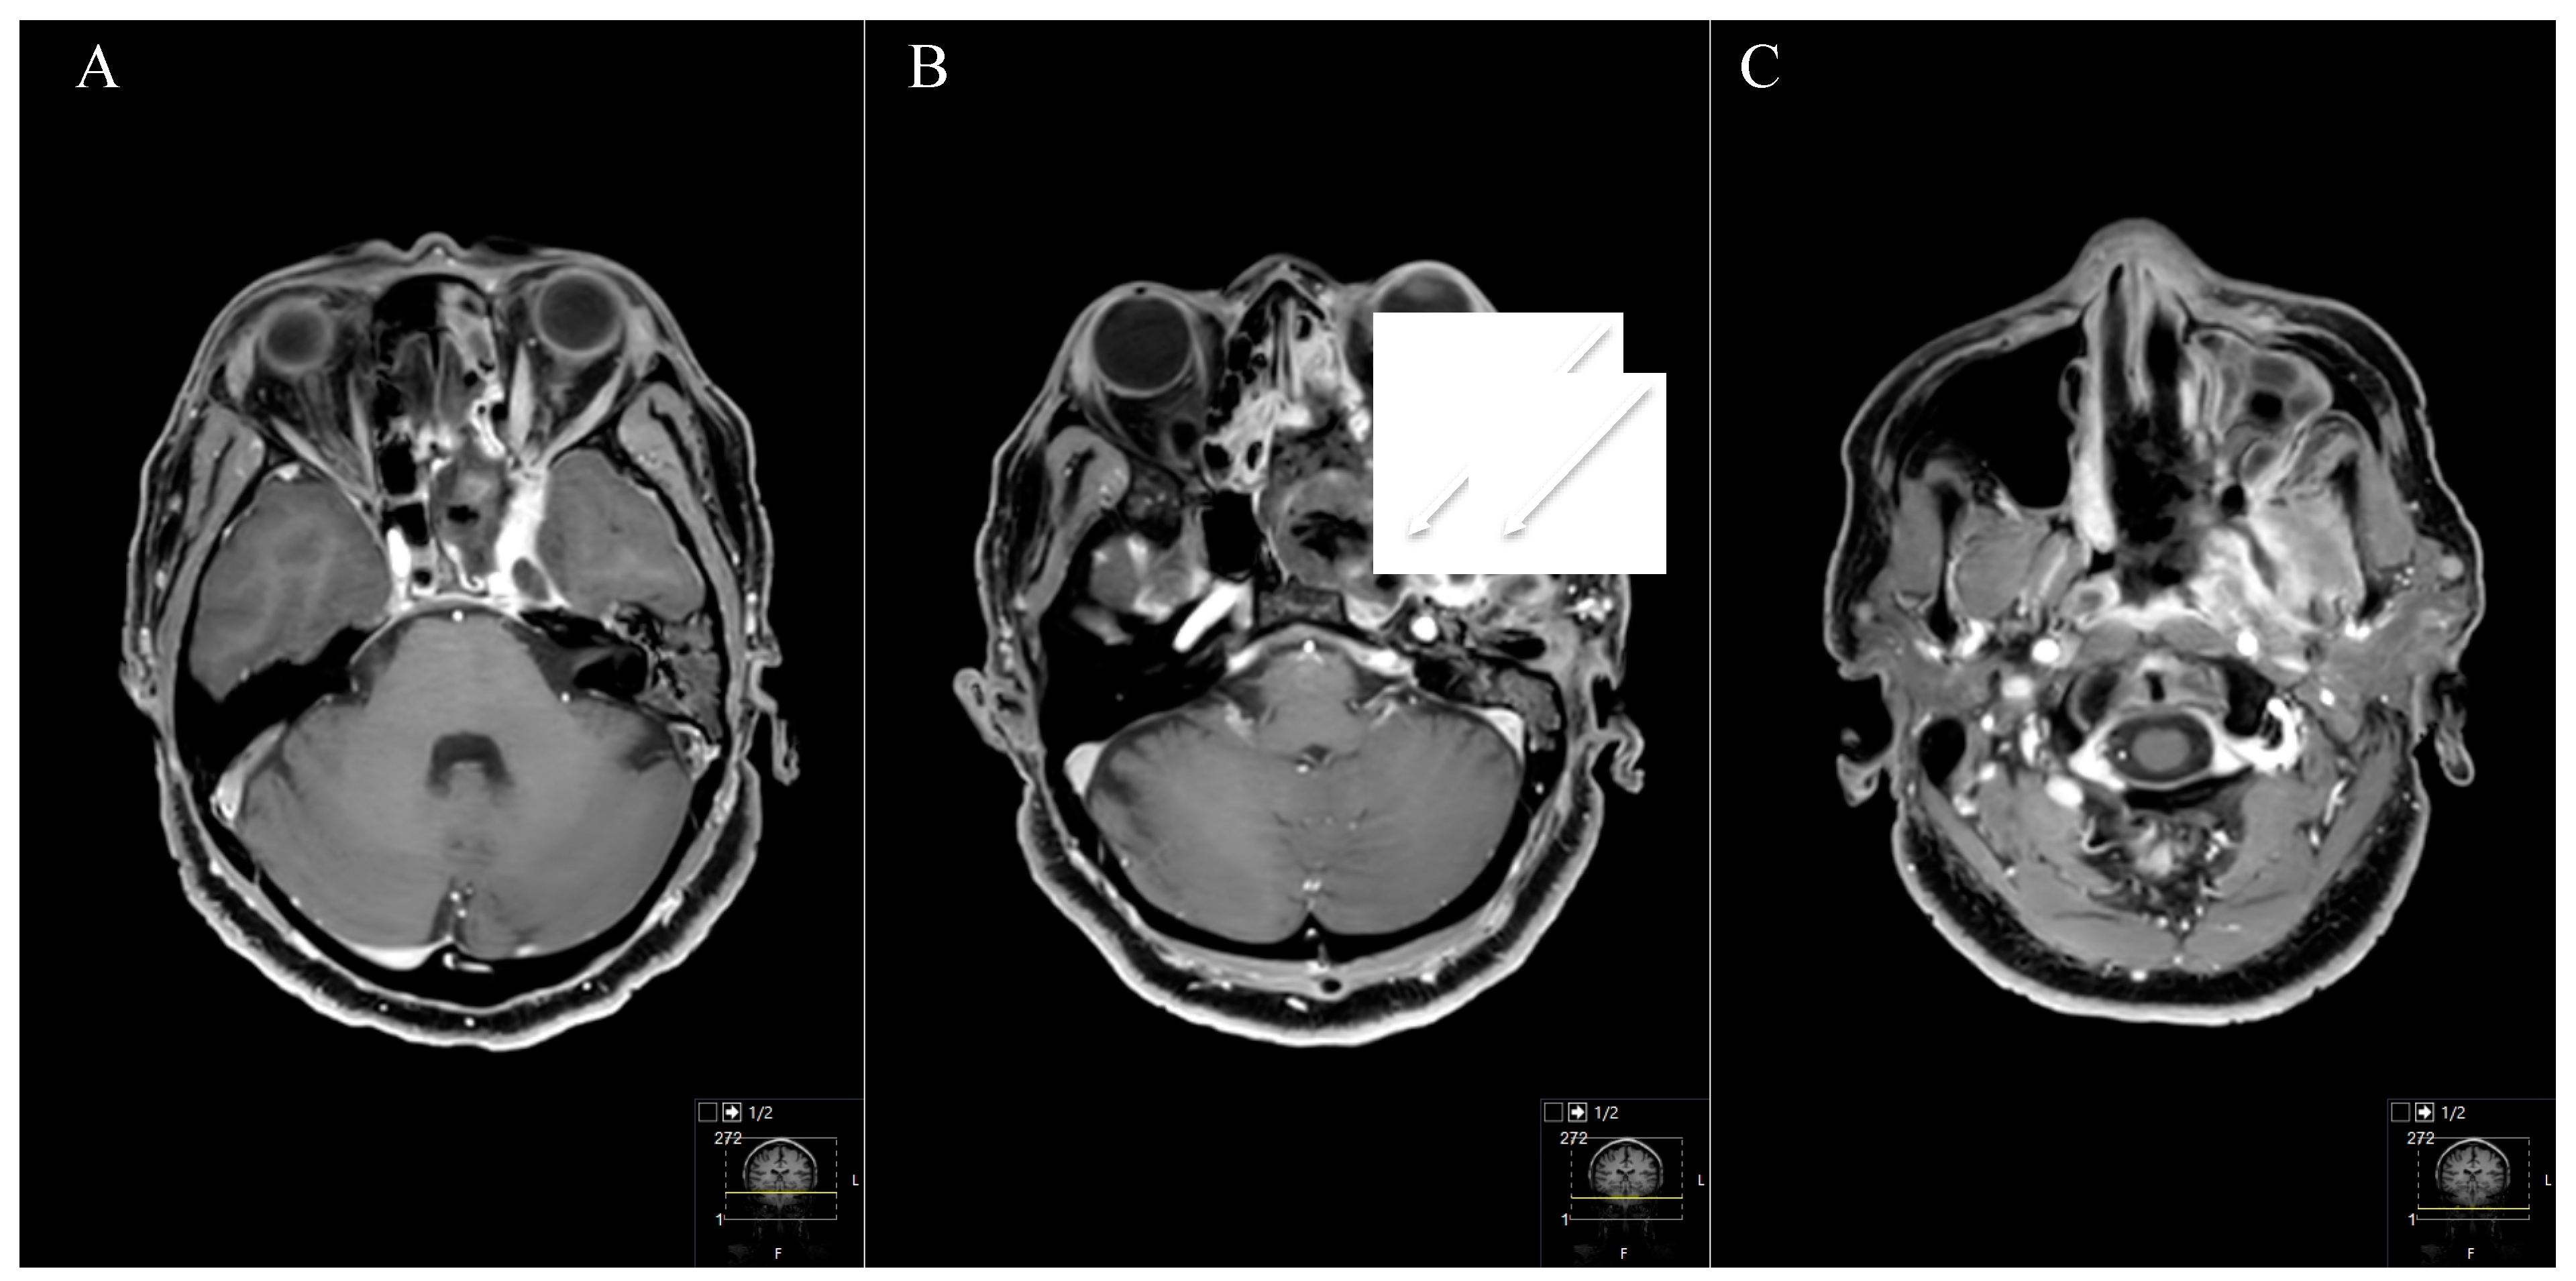

Figure 4. A 39-year-old male patient with neurofibromatosis type 2 presented with progressive vertigo, intermittent right facial pain and trigeminal hypesthesia (V1). (A) Preoperative axial and (B) coronal T1-weighted gadolinium-enhanced MRI, showing an impressive space-occupying cystic trigeminal schwannoma, involving the middle (MF) and posterior fossa (PF) through Meckel’s cave (Samii Type C). (C) Postoperative axial and (D) coronal MRI control, indicating complete resection via a two-stage technique; a modified Kawase and a retrosigmoid approach were performed. Postoperatively, no new deficits occurred and the patient recovered from the facial pain.